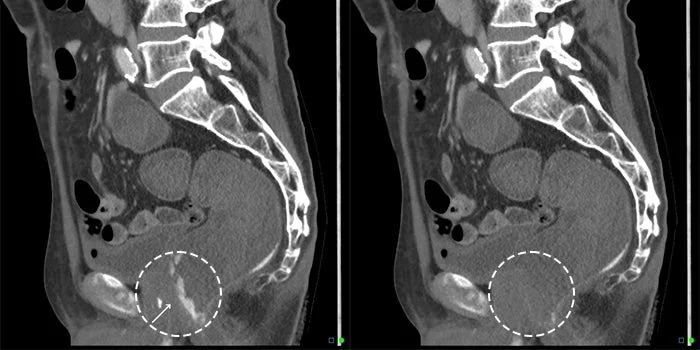

I’ve battled hemorrhoids for years—using sprays, pills, and even sitz baths with little success. But this spray changed everything. In just two days, the itching was gone, and after a week, the swelling had completely subsided. It’s so easy to use; I don’t even need to touch the affected area. What really shocked me was the before-and-after scans—my doctor showed me the difference on the MRI, showing a significant decrease in inflammation. This product has truly changed my life.

After years of suffering from pain and trying every spray, suppository, cream, and natural remedy on the market, I was honestly skeptical at first. But this cream lived up to its promise—fast relief and real, lasting healing. Within days, the pain and swelling began to subside. What completely convinced me was the follow-up scan my doctor showed me—the inflammation was significantly reduced compared to the previous scan. This is the first product I’ve used that truly works, and I finally feel like I’ve had my life back.